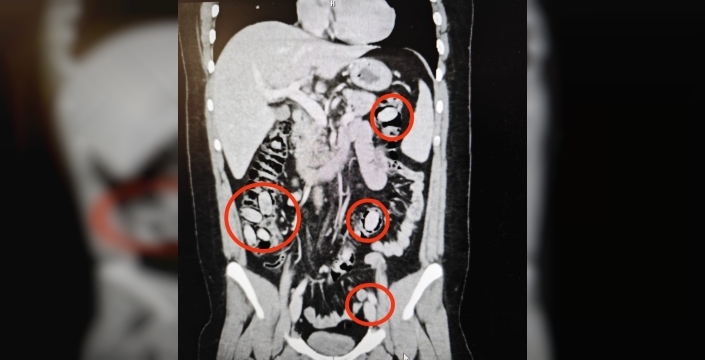

Eskişehir'de polisin dikkati sayesinde, midesinde 44 kapsül metamfetamin taşıyan yabancı uyruklu bir şahıs yakalandı. Şahıs, kent girişindeki çevirme noktasında durumundan şüphelenilmesi üzerine hastaneye götürüldü ve detaylı tetkikler sonucu uyuşturucu taşıdığı anlaşıldı.

Yapılan cerrahi müdahale ile şahsın midesinden 44 kapsül metamfetamin maddesi çıkarıldı. Tedavisinin ardından şahıs, mahkemece tutuklanarak cezaevine gönderildi. Bu operasyon, uyuşturucu maddelerin Eskişehir'de piyasaya sürülmeden ele geçirilmesini sağladı.